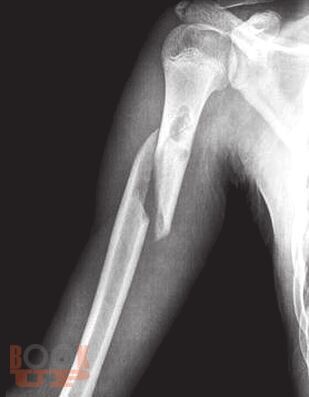

В пособии рассматриваются различные заболевания и травмы конечностей в аспекте их выявления лучевыми методами. Пособие составлено с учетом комплексного подхода к патологиям (костей и мягких тканей, суставов, сосудов, нервов) и диагностических методов (классического рентгеновского, КТ, МРТ, ультразвукового).